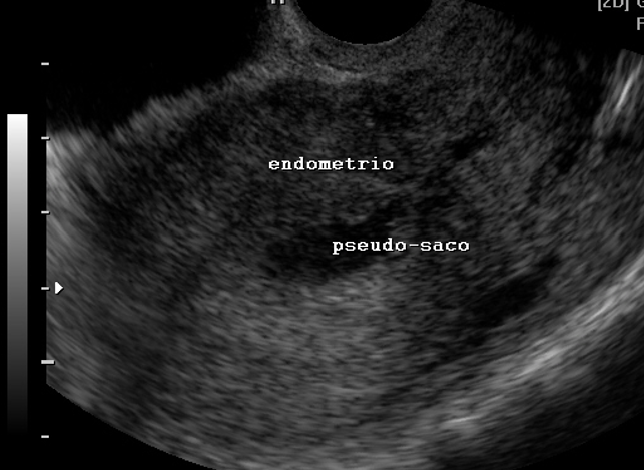

Gestação ectópica (US)

Ferramenta educacional baseada no NICE guideline NG126 (2019, atualização 2023), com abordagem conservadora. Ajuda a reconhecer sinais ultrassonográficos de gestação ectópica tubária e a lembrar a necessidade de correlação clínica e laboratorial.

Indica ectópica tubária (USTV)

Alta probabilidade (USTV)

Possível ectópica (USTV)